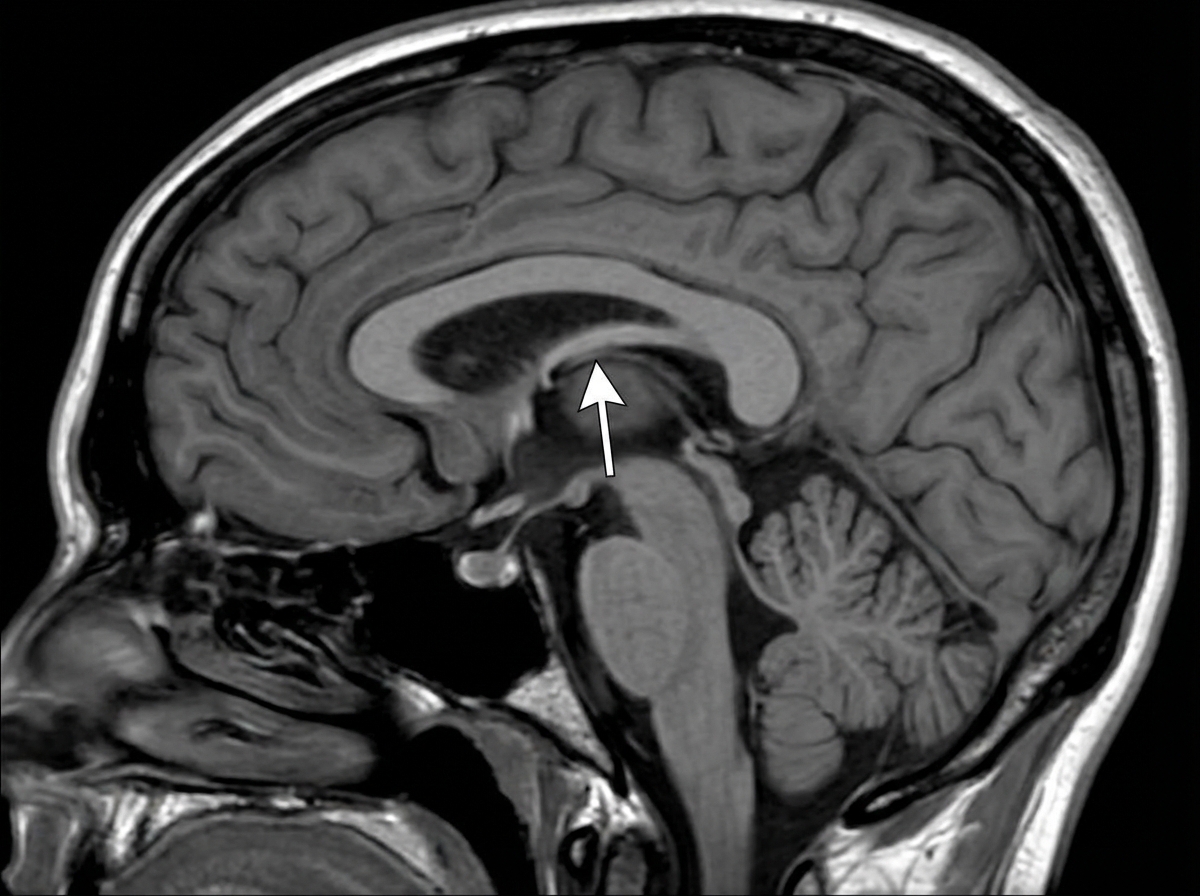

Explanation: ***Fornix*** - The arrow points to a C-shaped bundle of **nerve fibers** in the brain that acts as the primary efferent (output) pathway of the **hippocampus**, a crucial structure for memory. - It is located inferior to the corpus callosum and its position in the image is consistent with the anatomical location of the fornix. *Corpus callosum* - The corpus callosum is a large, **C-shaped nerve fiber bundle** located beneath the cerebral cortex in the longitudinal fissure, connecting the left and right cerebral hemispheres. - While visible in the image, the arrow specifically indicates the structure immediately beneath it, which is the fornix, not the corpus callosum itself. *Pineal gland* - The **pineal gland** is a small endocrine gland located in the epithalamus, near the center of the brain, behind the thalamus. - Its position is medial and inferior to the structure indicated by the arrow. *Splenium* - The **splenium** is the posterior, thicker part of the **corpus callosum**, forming its most caudal end. - The arrow points to a more anterior and inferior structure than the splenium. *Septum pellucidum* - The **septum pellucidum** is a thin, vertical membrane separating the anterior horns of the left and right lateral ventricles. - It is located superior and anterior to the fornix, positioned between the corpus callosum above and the fornix below, which is different from the structure indicated by the arrow.